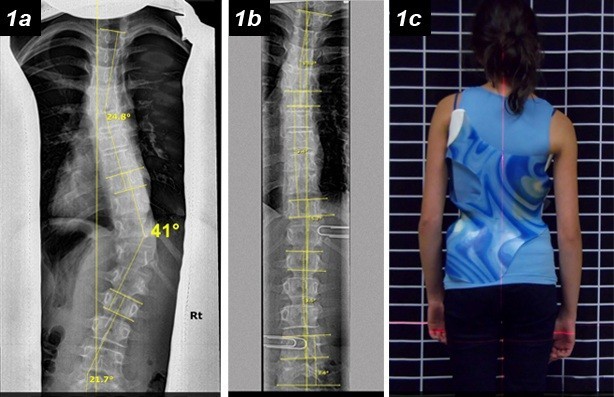

تقييم اعوجاج العمود الفقري بعد 6 أشهر بدون الحزام: أهم مؤشر لتحديد نجاح العلاج يُعد اعوجاج العمود الفقري لدى المراهقين من أكثر الحالات التي تُقلق الأهل، خاصة عند بدء العلاج بالحزام الطبي (الدعامة). وغالبًا

كيف يرى المريض والأهل شكل الجسم مع حزام اعوجاج العمود الفقري؟ وتأثير ذلك على تقبل العلاج والالتزام يُعد اعوجاج العمود الفقري من الحالات التي لا تؤثر فقط على شكل الظهر، بل تمتد آثارها إلى

التنبؤ بنتائج حزام اعوجاج العمود الفقري :الفرق بين الأشعة داخل الحزام وخارجه يُعد اعوجاج العمود الفقري عند المراهقين من أكثر حالات التشوهات الشائعة خلال مرحلة النمو، ويُعرف طبيًا باسم “الجنف مجهول السبب عند المراهقين”.